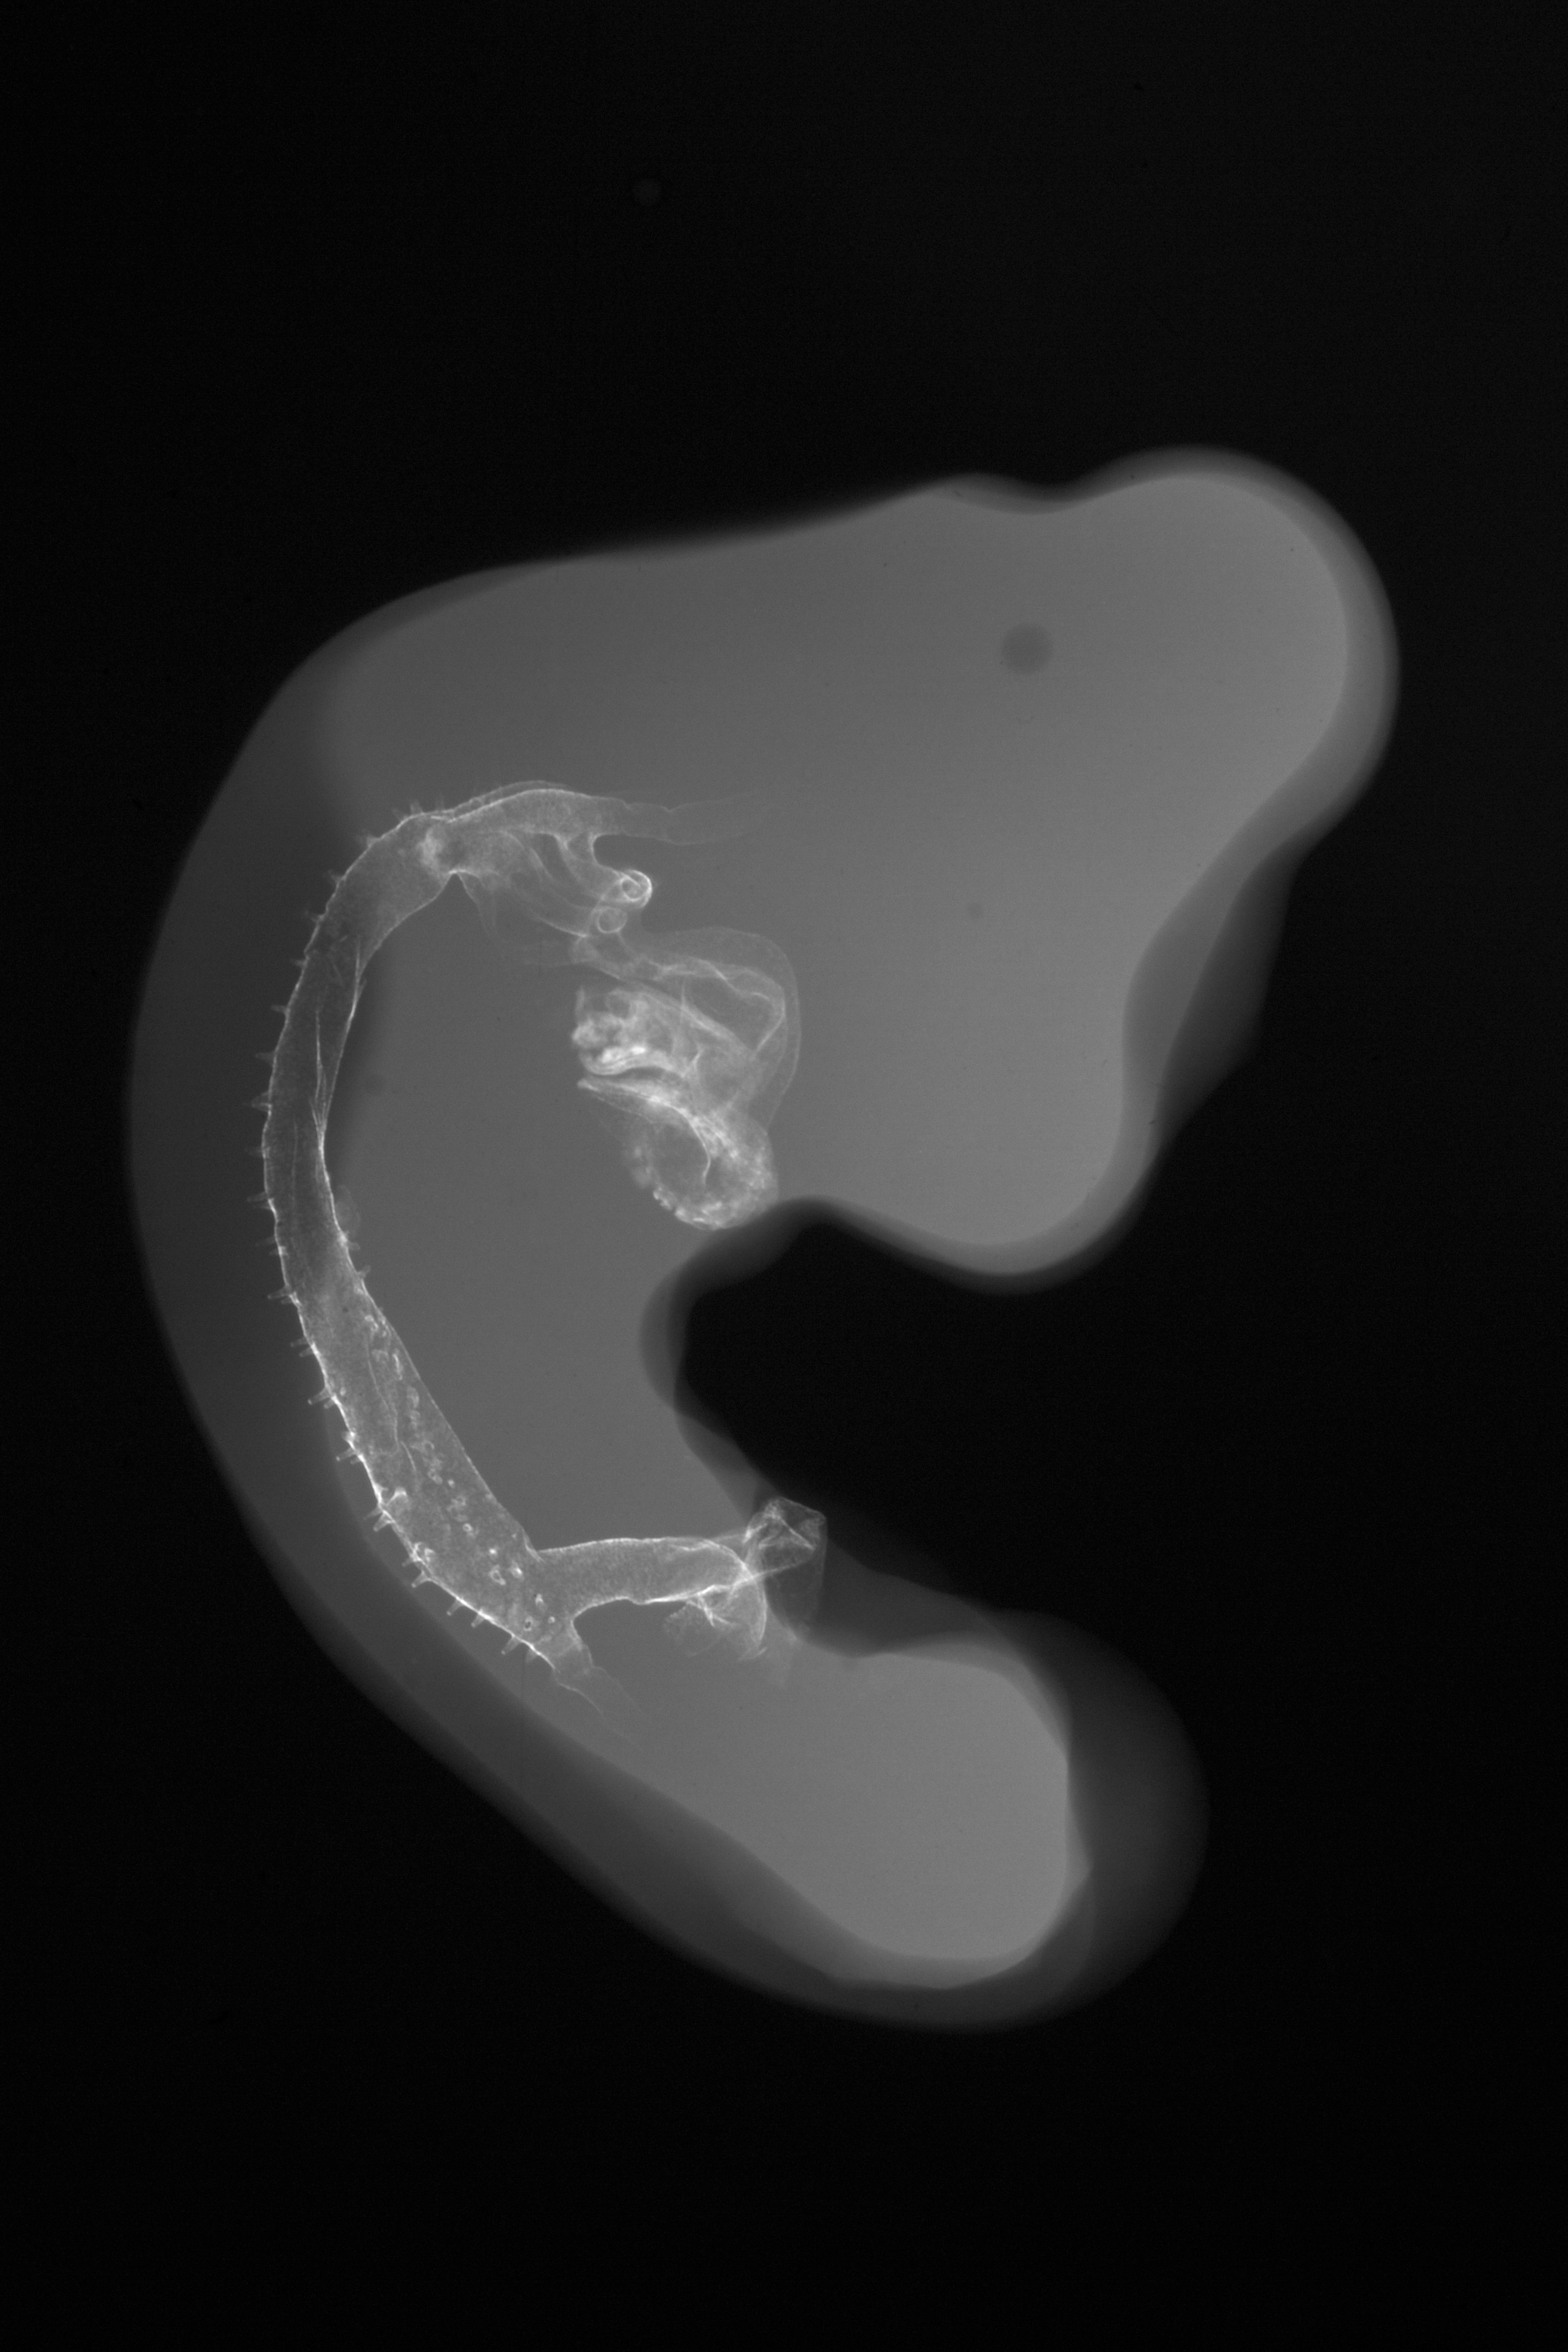

Chick Embryo Microangiography

Hamburger-Hamilton (HH) Stage 22 (approx. 4 days)

Stereo X-Ray Micrographs